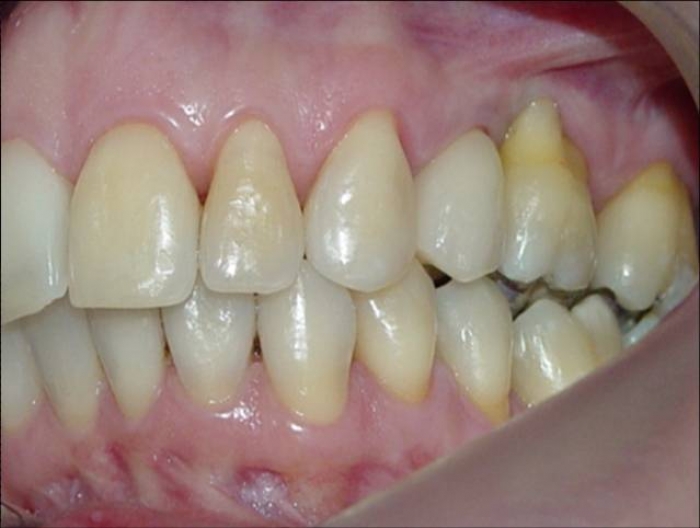

Imagens iniciais, observando a ausência do pré molar superior